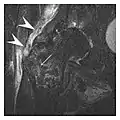

The sacrum is usually masked by overlapping bowel gas in conventional radiographs, and the subtle radiographic findings are usually nondiagnostic and even misleading. The characteristic "H" pattern has been correlated with biomechanical models of patient activities. The vertical parasagittal planes correspond to the region of maximal stress during walking, while the horizontal fracture develops later, secondary to the loss of lateral support by parasagittal fractures. MRI is the primary imaging technique in this case, with the most common MRI pattern showing bone marrow edema and a fracture line (Figure 12). Coronal views are quite contributive in sacral fractures, allowing the detection of the horizontal component, especially with fluid-sensitive sequences. Although the sacrum is the most commonly involved, pelvic insufficiency fractures are often multiple, and other typical locations should be mentioned.[1]

Proximal femoral fractures usually occur in osteoporotic patients, and their signs include subtle neck angulation, trabecular angulation, and subcapital impaction line. A frog-leg lateral view may be helpful if the greater trochanter is short enough. However, positioning can be difficult because of hip pain. In patients with strong suspicion of proximal femoral fracture and negative radiographs, MRI limited to coronal T1 W images and scintigraphy can be highly valuable (Figures 13 and 14). Such an option, with limited examination time, is cost-effective and allows reliable exclusion or confirmation of the diagnosis, preventing an unnecessary stay at the hospital or delayed treatment. Moreover, MRI helps to detect soft tissue abnormalities which are more frequently seen in femoral, acetabular, and pubic injuries than sacral lesions. Concomitant fractures are also frequently seen in typical pelvic sites.[1]

a

b

Figure 13: Partial osseous avulsion of the gluteal muscles at the greater trochanter in a 59-year-old man who presented with the right hip pain without a history of trauma. Lauenstein view and anteroposterior and radiographs (not shown) did not show an obvious fracture line or disruption of bony contours in the acetabulum or the right femoral neck. (a) Coronal T1-weighted MRI displays an incomplete fracture line extending partially from the greater trochanter (arrow). (b) Coronal short tau inversion recovery MRI shows heterogeneous hyperintensity in the same region (arrow) as well as hyperintensity within the gluteus medius and minimus muscles (arrowheads) consistent with tissue edema and hematoma.[1]

Figure 14: Subcapital insufficiency fracture in a 55-year-old man with a left hip pain without a history of trauma. Anteroposterior and Lauenstein view radiographs centered on the left hip do not show an obvious fracture line, but mild acetabular osteophytosis was noted consistent with hip osteoarthritis (not shown). (a) Coronal T1-weighted MRI shows a linear low-signal band through the femoral neck corresponding to a fracture line (arrowheads). (b) Bone scintigraphy shows focal uptake (arrow) corresponding to the fracture.[1]